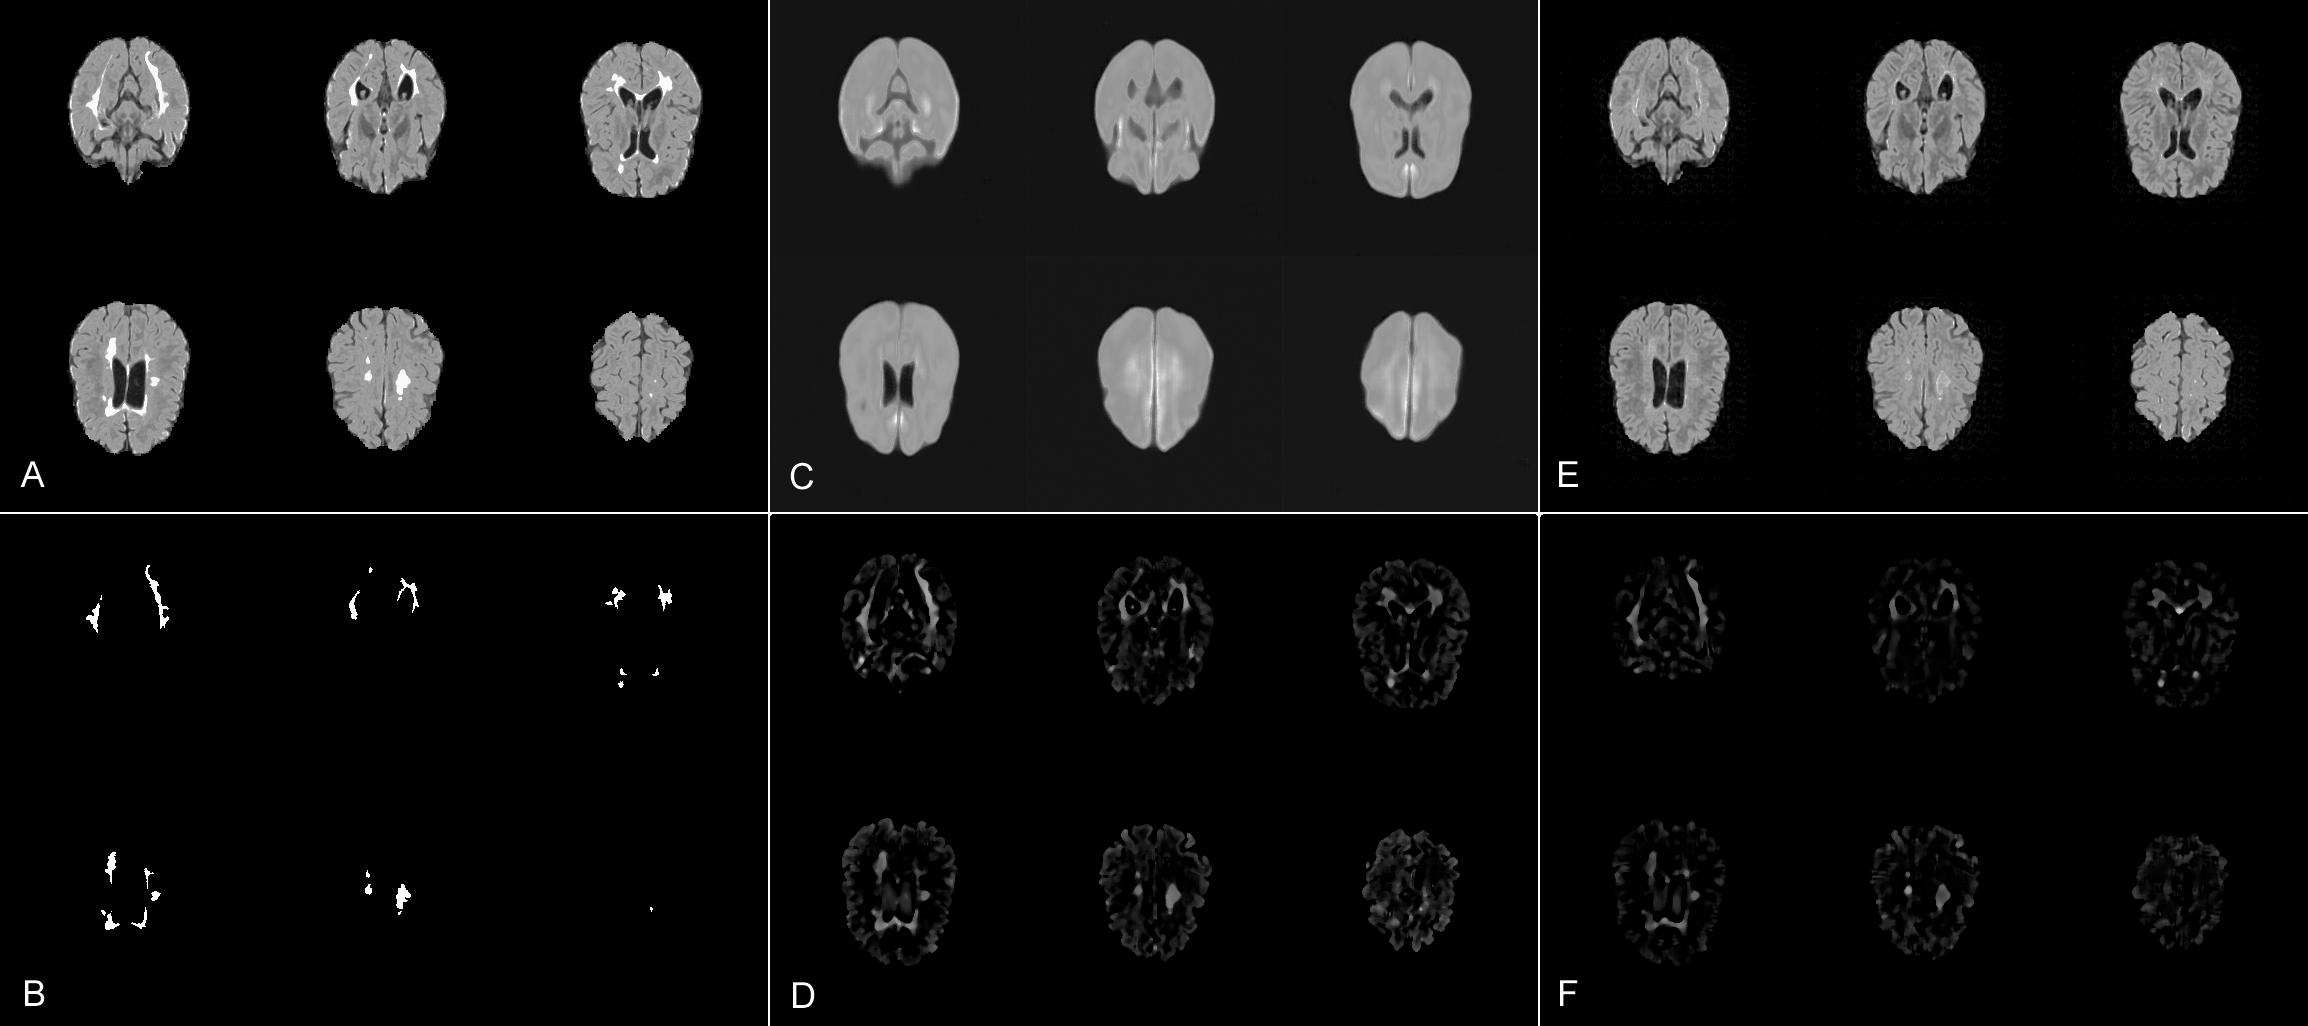

Refer to caption

Figure 2: Visual results. A: input; B: ground-truth segmentation; C: reconstruction from a normal AE; D: median-filtered residuals from C; E: reconstruction from our SSAE; F: median-filtered residuals from E. The high fidelity facilitated by our scale-space approach leads to fewer unwanted residuals.

Next, we compare variants of AEs, i.e. dense AE, spatial AE and a VAE, against their scale-space counterparts in terms of their reconstruction capabilities. Again, all corresponding models share the same architecture and model complexity for a fair comparison. To measure fidelity, we collect the pixel-wise 1subscript1\ell_{1}-errors among all healthy validation input slices and their reconstructions, normalized by the total number of pixels. Fig. 3 shows the corresponding statistics on 𝐫0=256×256subscript𝐫0256256\mathbf{r}_{0}=256\times 256px, 𝐫1=128×128subscript𝐫1128128\mathbf{r}_{1}=128\times 128px and 𝐫2=64×64subscript𝐫26464\mathbf{r}_{2}=64\times 64px. The upper limit of 256×256256256256\times 256px was set by our training data 𝒟healthysubscript𝒟𝑒𝑎𝑙𝑡𝑦\mathcal{D}_{healthy}. In comparison to their AE counterpart, all scale-space models show substantially lower reconstruction errors at all scales. As expected, reconstruction errors increase with image resolution, as the modeling task becomes more complex. The lowest error is achieved by a spatial SSAE, which reconstructs data almost perfectly due to the low level of compression in its bottleneck. Interestingly, a dense SSAE is on par with a spatial AE, although it loses any spatial cues in its latent space. The achieved high fidelity can also be seen in our visual results (Fig. 2).